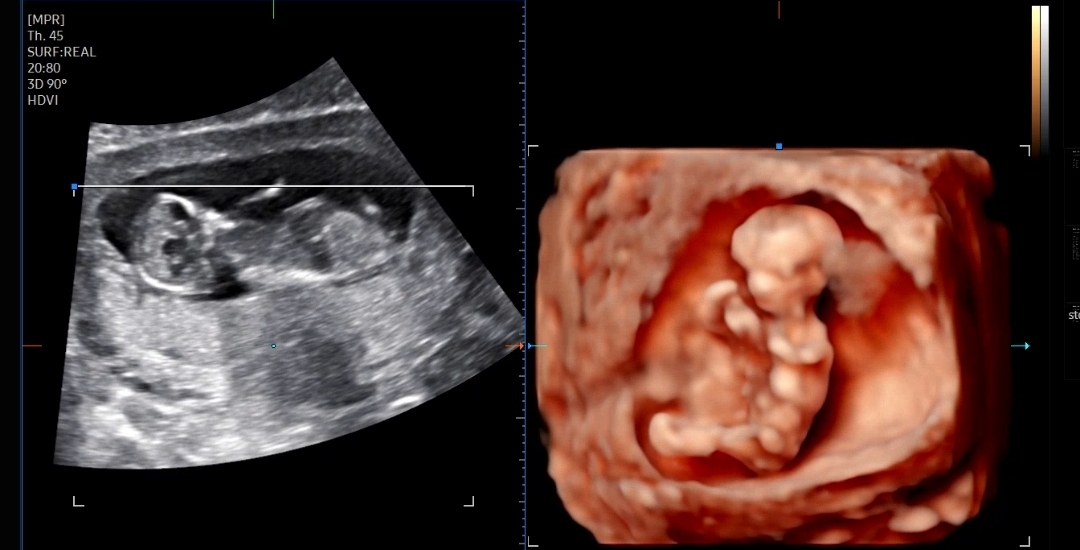

처음으로 그나마 사람같이(?) 보이던 입체 초음파 ㅋㅋ

그동안 입체 초음파는 거의 사람형태가 아니어서 굳이 안 보여주셔도 되는데 싶었는데

이번에 처음으로 그나마 사람의 형태 비스무리하게 보였다